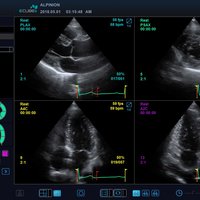

• P1-5CT (1-5 MHz) für Ultraschalluntersuchungen in Bereichen Kardiologie, Abdomen, transkraniell

• SP3-8T (3-8 MHz) für Ultraschalluntersuchungen in Bereichen Kardiologie, Abdomen, transkraniell